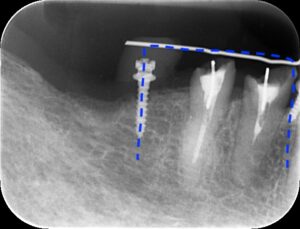

レントゲン画像です。青点で囲ったように鉄棒状に

なっています。

画像の丸点の部分ですが歯につけたフックと棒が

ぶつかりかなり挺出していることがわかります。

また青の横点線部分は歯茎ごと挺出しています。